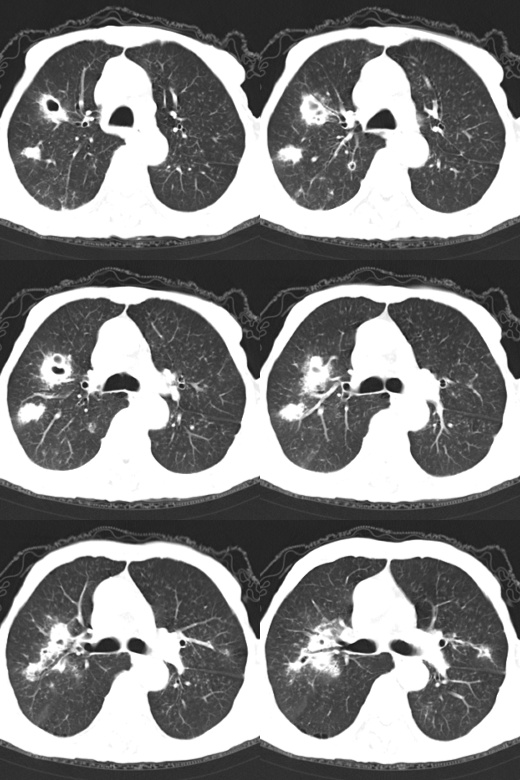

70岁男性,石匠工作史20+年,因胸痛、咳嗽数日就诊。无喀痰或痰血,无发热、盗汗。无明显腹痛。

局部薄层扫描:

双上肺多发结节性空洞边沿有毛刺,考虑韦格氏肉芽肿,不除外肺泡癌。建议进一步检查

1、双肺多发囊性转移瘤可能性大;2、左上腹巨大囊性占位,壁厚且多发钙化,来源肾上腺可能,不排除恶性;3、左肾囊肿。

1)两肺多发病灶、纵隔及腹膜后淋巴结肿大,不排除淋巴瘤。2)脾脏囊肿可能。3)左肾囊肿。